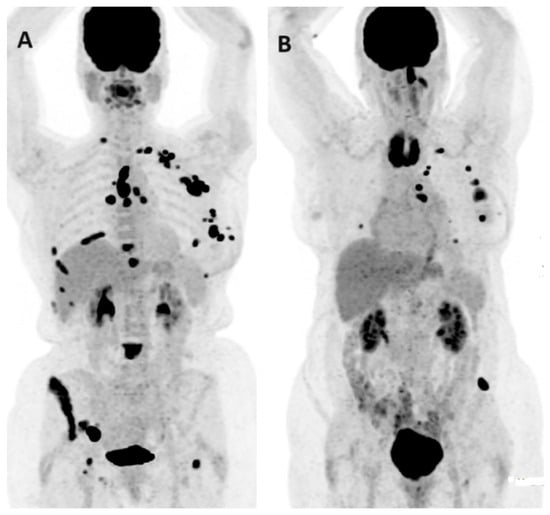

- Venema, C.M.; Mammatas, L.H.; Schröder, C.P.; Van Kruchten, M.; Apollonio, G.; Glaudemans, A.W.J.M.; Bongaerts, A.H.; Hoekstra, O.S.; Verheul, H.M.; Boven, E.; et al. Androgen and Estrogen Receptor Imaging in Metastatic Breast Cancer Patients as a Surrogate for Tissue Biopsies. J. Nucl. Med. 2017, 58, 1906–1912. [Google Scholar] [CrossRef] [PubMed]

- Jacene, H.; Liu, M.; Cheng, S.C.; Abbott, A.; Dubey, S.; McCall, K.; Young, D.; Johnston, M.; Abbeele, A.D.V.D.; Overmoyer, B. Imaging Androgen Receptors in Breast Cancer with 18F-Fluoro-5α-Dihydrotestosterone PET: A Pilot Study. J. Nucl. Med. 2022, 63, 22–28. [Google Scholar] [CrossRef] [PubMed]